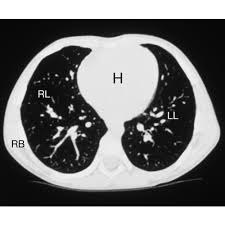

One of our lung nurse navigators will answer your questions, assist you with a referral to a primary care physician, and help you schedule your screening. People who already have symptoms that might be caused by lung cancer may need tests such as ct scans to find the underlying cause, which in some cases may be cancer. 95% of nodules found are benign. While not all detected lung nodules should be reported, radiologists. A computer then combines these images into a detailed picture of your lungs. But this kind of testing is for diagnosis and is not the same as screening. Doctors can use a ct scan to look for lung cancer. When you get a ct scan, you lie on a table while a machine rotates around your. A lung scan using either a ct scan or an ultrasound can detect these early signs of cancer. If you are a smoker, it is highly recommended to have a ct scan every 3 months. Computed tomography (ct) scans detect tumors, but do not determine whether they are malignant or not. This is because there are very few symptoms related to the condition until it gets to an advanced level. While it might seem obvious to assume that finding small tumors reduces one's likelihood of dying from lung cancer , this is incorrect.

Ct scans are very sensitive in detecting lung cancers, and are the most common way in which cancers are diagnosed in the lungs. Need help kicking the tobacco habit? On the other hand, patients who've had surgeries related to their lungs or lung cancer are advised to take more scans than regular smokers. Fundamental to the diagnosis of lung cancer in ct scans is the detection and interpretation of lung nodules. A bone scan can help show if a cancer has spread to the bones. Thanks to advances in medical technology, a computed tomography (ct) scan now allows doctors to detect lung cancer even during its early stages. If the test finds cancer, treatment can start early. This significantly improves patients' chances of recovering from the disease and lowers related treatment costs.